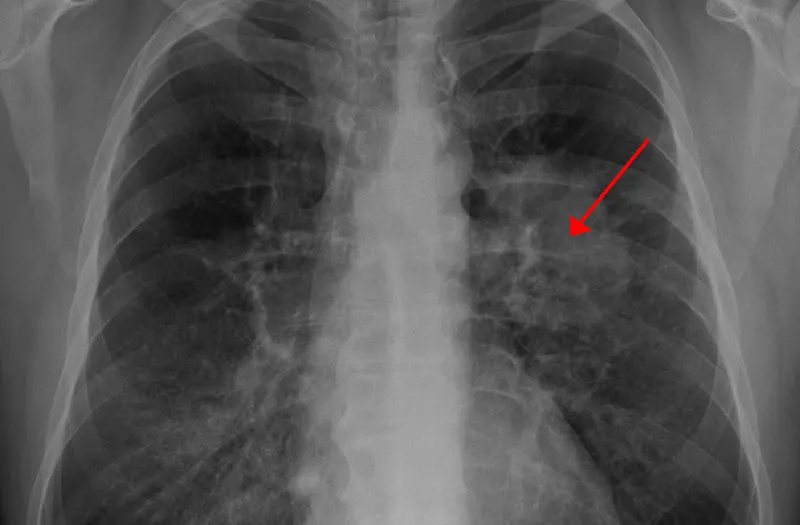

Most patients with benign lung tumors have no symptoms (less than 5%). Studies show that more than 90% of cases are discovered incidentally on chest X-ray or CT scan.

Detecting a lung tumor is often a diagnostic challenge for physicians, especially when tumors are incidentally found on imaging such as a chest CT scan. Determining whether a lung tumor is benign or malignant usually requires a biopsy.

In addition to medical history, physical examination, and imaging (X-ray or CT scan), doctors may recommend several tests to identify the nature of the lung tumor, its underlying cause, and potential complications. These may include: